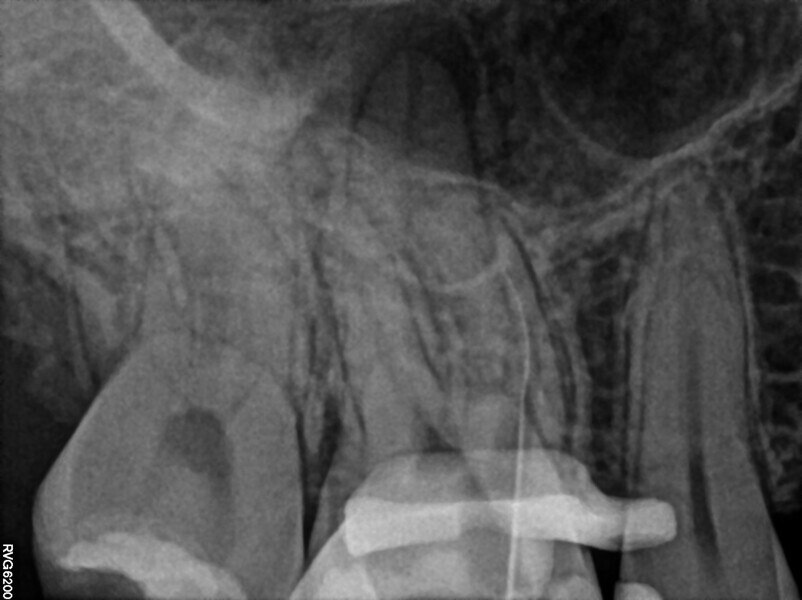

During the consultation appointment, a CBCT scan was performed. It revealed a small osteolytic lesion around the mesial root, suggesting the possibility of achieving patency in the root canals in the mesial root. Around the distal root, there were no signs of the lesion, which indicated that the mesial root was the cause of the symptoms. The radiographic examination also revealed a broken lentulo in the MB canal (Fig. 16).

Figs. 16 a & b

The patient was scheduled for the first appointment to remove the lentulo and scout the canals. After local anaesthesia and placement of the dental dam, the restoration was removed. In the orifices of all three root canals, Endomethasone N was present. This cement was removed with a U-file ultrasonic tip and sodium hypochlorite 5,25%. The tip of the lentulo was exposed. Unfortunately, the lentulo had broken not in the cement but in an unprepared part of canal, which probably had had vital pulp on the day of the treatment because the entire lentulo fragment was surrounded by calcified tissue and was hidden behind the coronal curvature. At this level, the decision was made to use constant flow of sodium hypochlorite 5,25% and laser activation for 10–15 minutes. The calcified tissue was dissolved, and the lentulo was removed. A periapical radiograph was performed to confirm that the entire fragment had been retrieved (Fig. 17). Owing to the gag reflex, this procedure was very difficult. After removing the broken instrument, 17% EDTA and sodium hypochlorite 5,35% was activated with SkyPulse in AutoSWEEPS mode in a few 15- to 20-second cycles, and patency was checked with a hand file. The periapical radiograph revealed that the file engaged deeper than the predicted length of the previous root canal filling (Fig. 18). The tooth was closed with a temporary composite restoration, and the patient was scheduled for a second appointment.